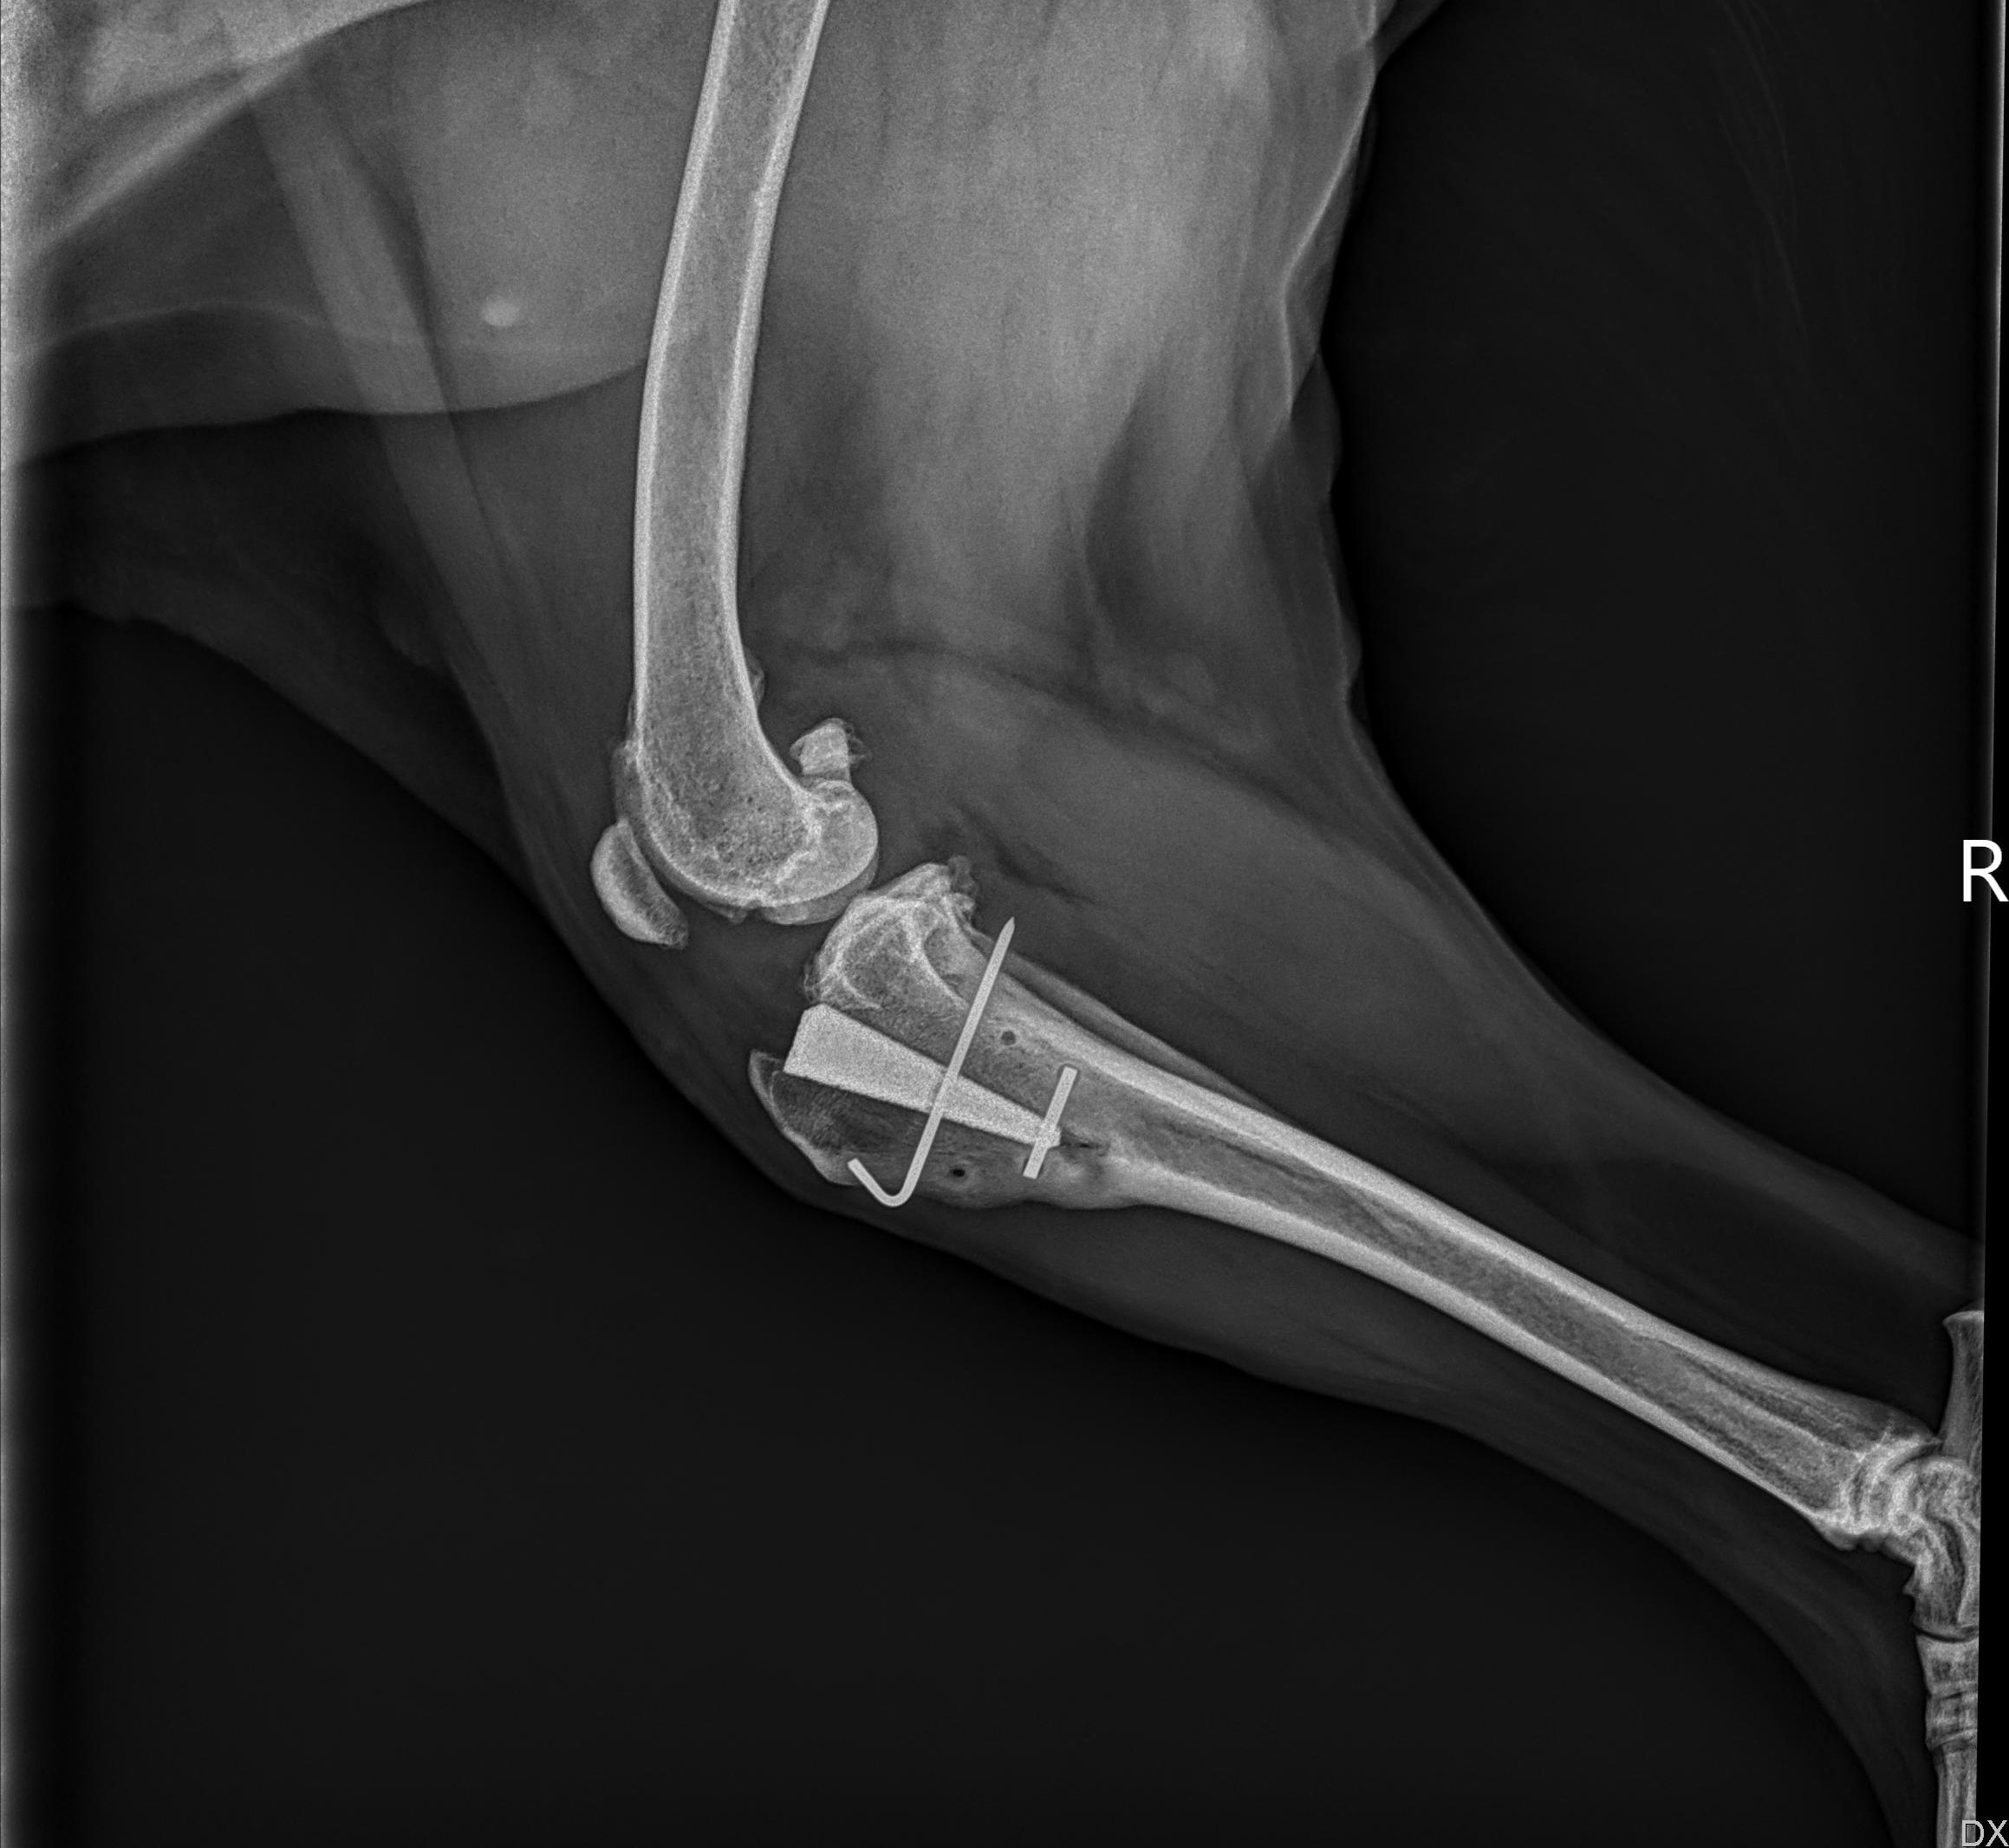

Das letzte Röntgenbild sieht sehr gut aus.

Unsere Süße hat vor 14 Tagen beim Toben auf dem Spaziergang das Kreuzband am anderen Bein zerrissen. War ja zu erwarten, aber wir hatten doch gehofft, dass es nicht passiert.

2 Tage später wurde sie operiert, diesmal eine TPLO. Die Klinik hat jetzt nen Chirurgen der das kann, damals schoben sie ja vor, es hätte das notwendige material nicht gegeben wegen Kuhrona.

Die ersten 3 tage machte sie sich supergut, lief auch schön mit dem bein......bis zur nachuntersuchung am 4. tag. Das beugen und strecken fand sie wohl nicht so toll.....Fortan hatte sie nur noch 3 Beine und schien auch starke schmerzen zu haben, Hab ihr dann gegen abend immer noch cbd öl gegeben. Gestern fing sie dann an das Bein wieder mehr zu belasten. Heute nun wurde der Faden gelöst. Und nun läuft sie wieder ohne Probleme. Bin ich froh....Ihren Rhodonit Schädel hat sie wieder im Schlafplatz.